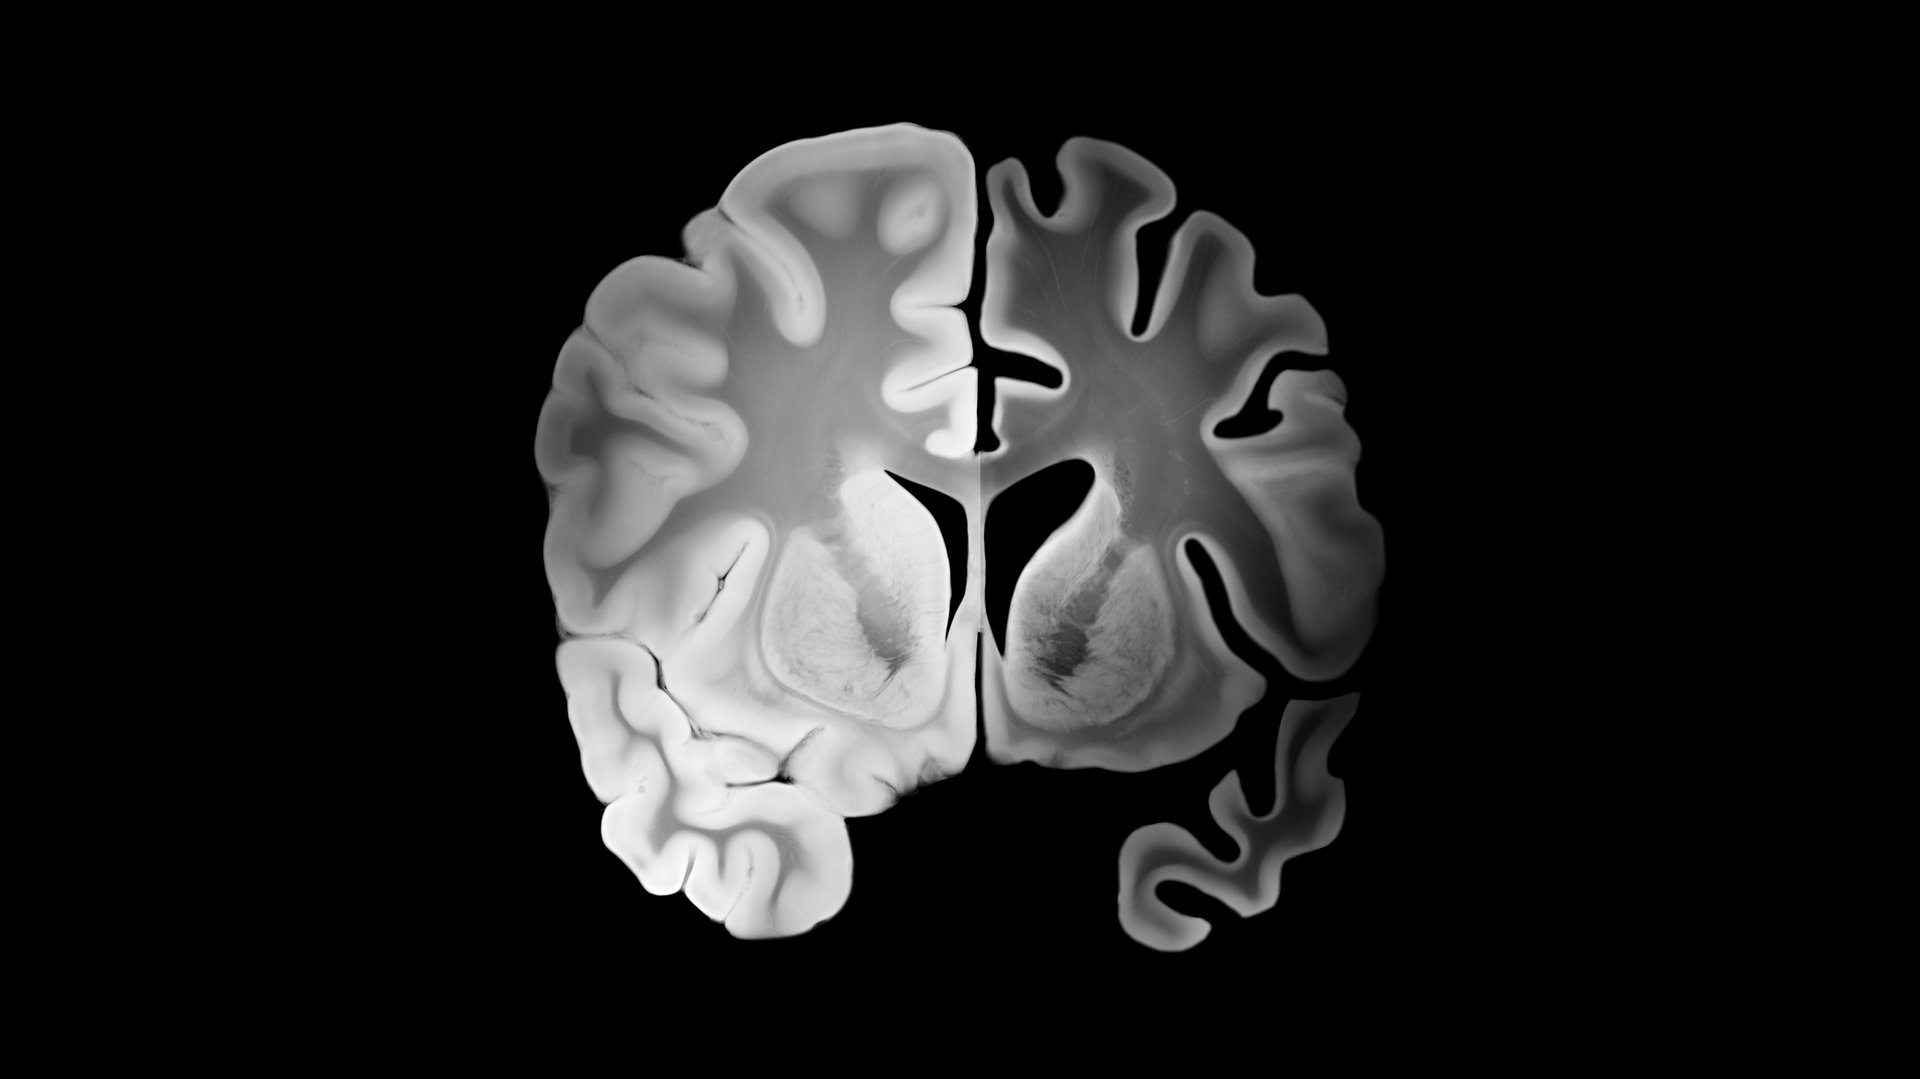

Alzheimer left hemisphere compared to healthy right hemisphere in a coronal brain slice with cortical thinning, widened sulci, enlarged ventricles and progressive brain tissue loss.